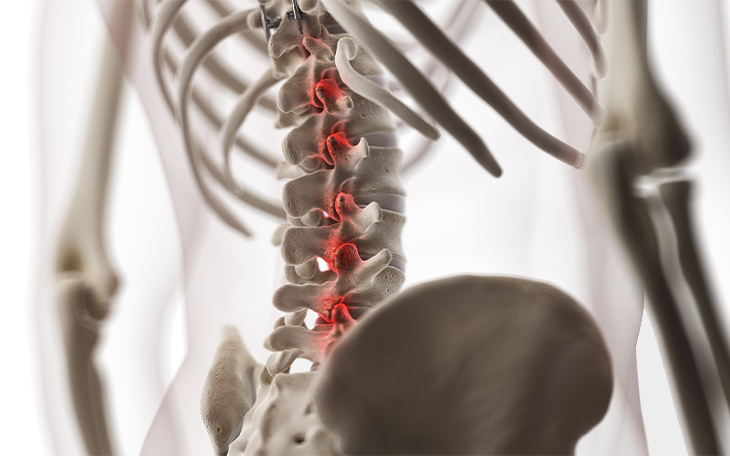

Erkrankungen der Lenden- und Brustwirbelsäule

Die Lenden- (LWS) und Brustwirbelsäule (BWS) ist täglich hohen Belastungen ausgesetzt und anfällig für verschiedene Erkrankungen. In dieser Kategorie finden Sie eine Übersicht typischer Beschwerden, ihrer Ursachen, Symptome und Behandlungsmöglichkeiten – von Bandscheibenvorfällen über Wirbelgelenksarthrose bis hin zu muskulären Dysbalancen.